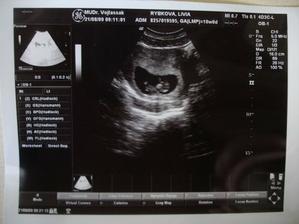

My a náš prvý očakávaný anjelik

Po roku dlhého skúšania sa nám konečne podarilo...Sme s manželom veľmi šťastní a nevieme sa našeho prvo-rodeného bábatka dočkať.